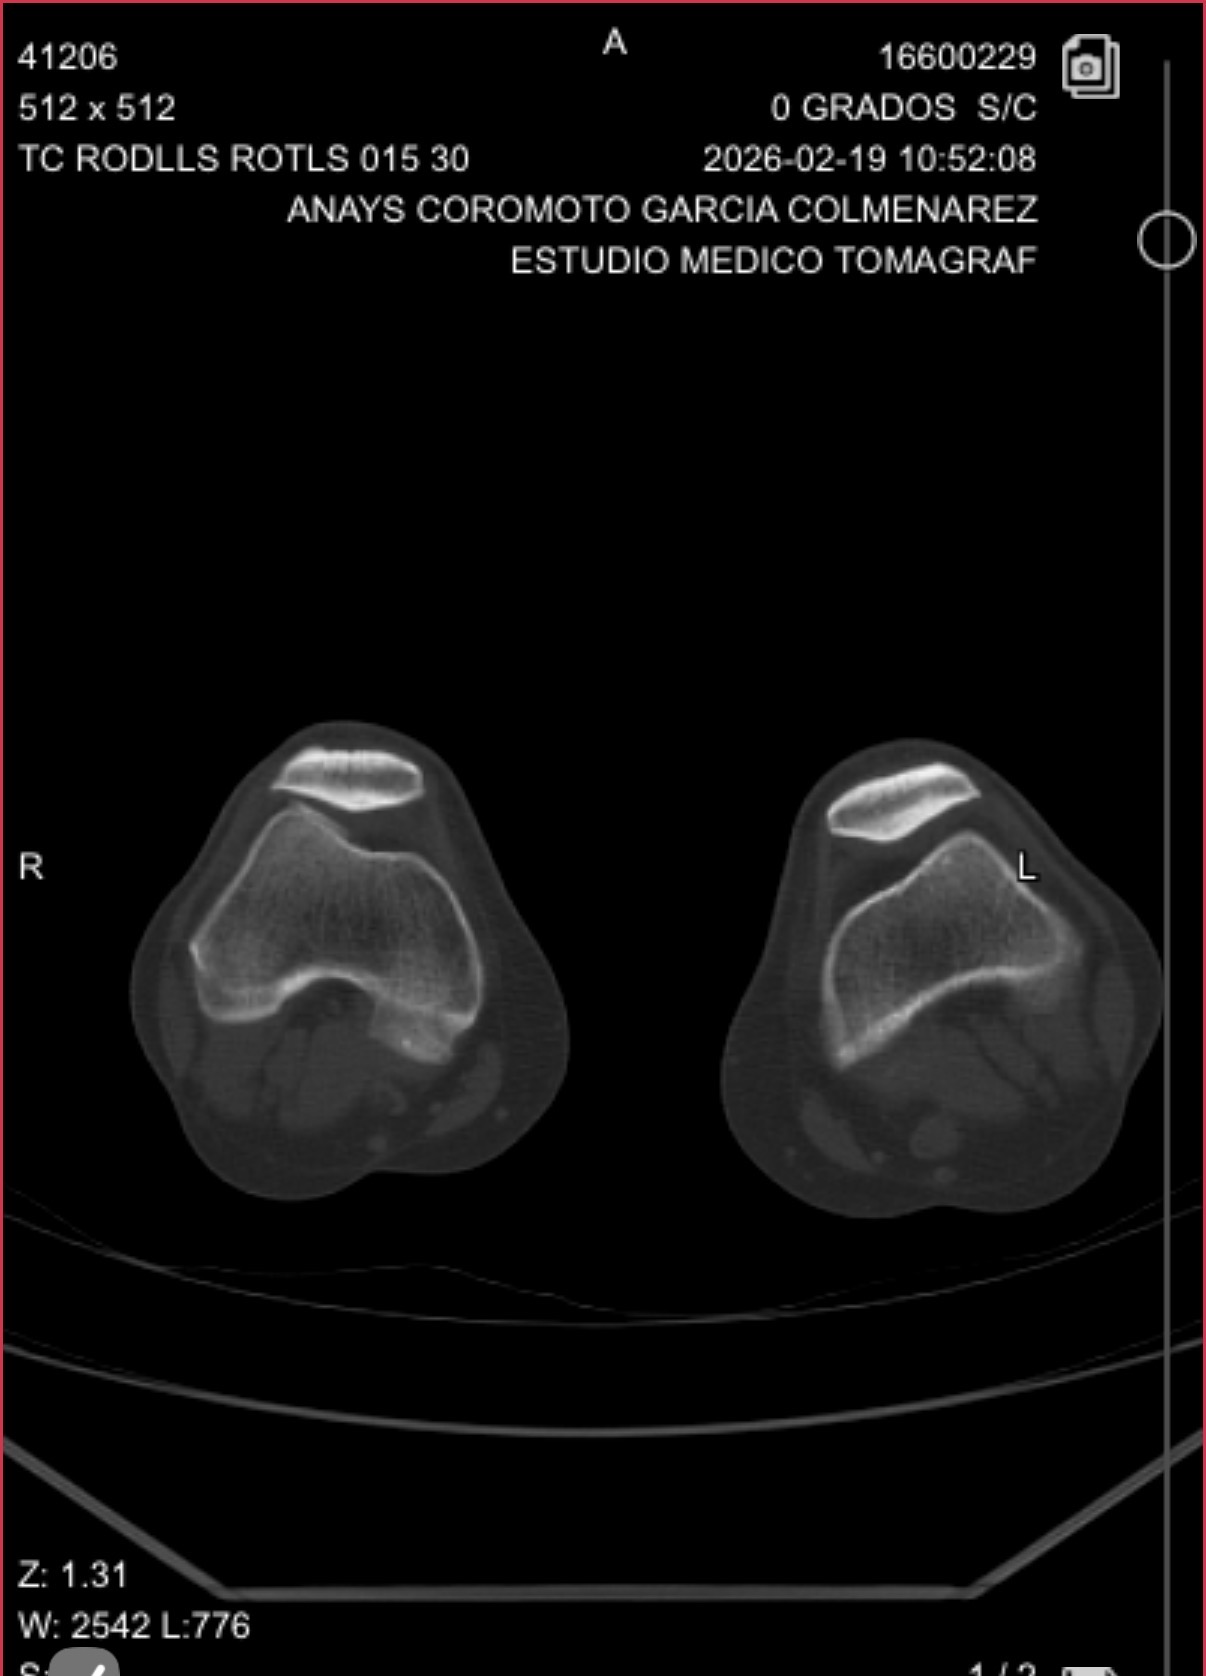

Tac de rodilla